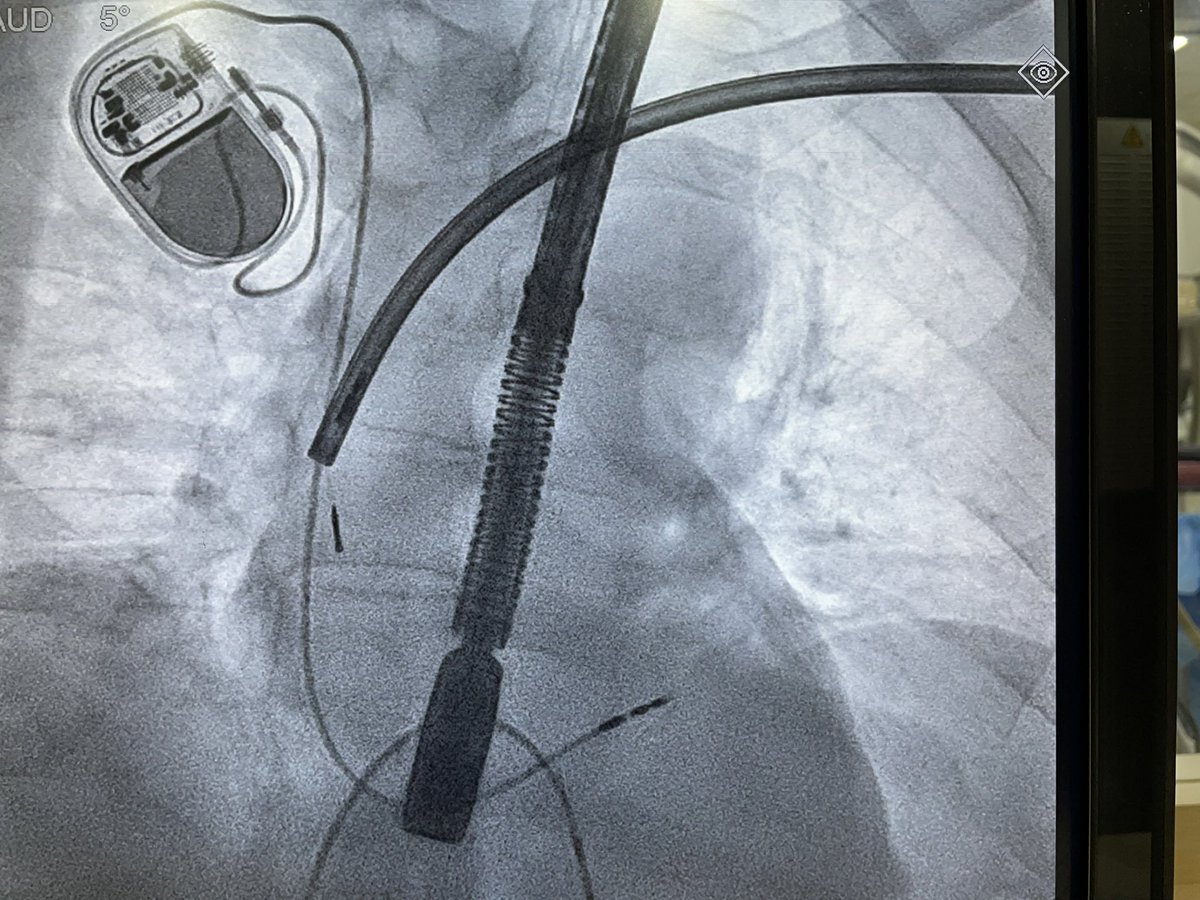

Dual chamber Leadless AVEIR pacemaker at Apollo Chennai - first in Tamilnadu and Apollo Group. - innovative, revolutionary, minimally invasive solution that ensures faster recovery and lasting comfort with physiological pacing. @Pacemaker @Apollo_Chennai @AbbottNews